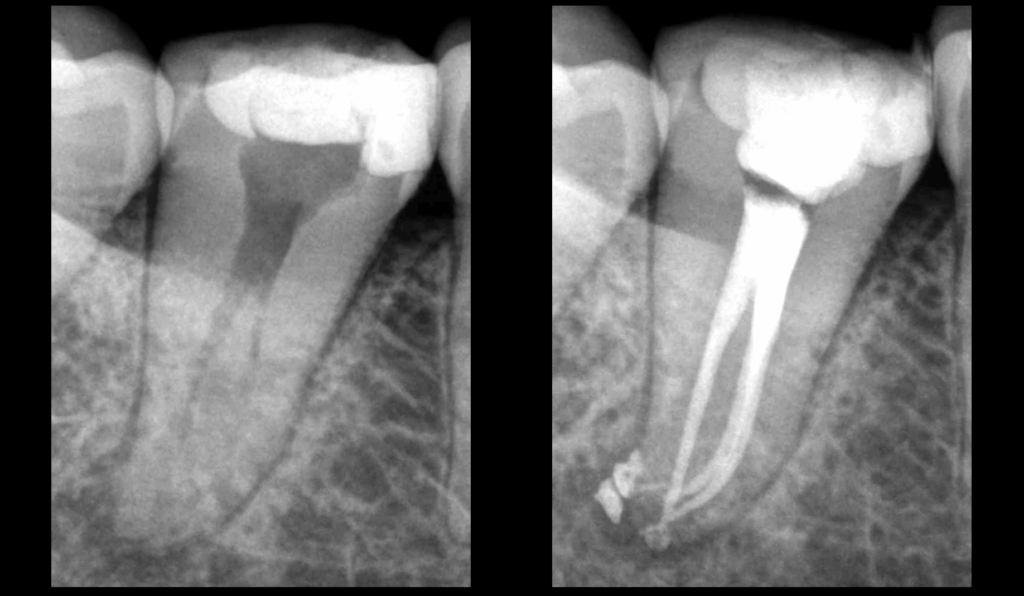

🦷 La fluidité d’un biomatériau d’obturation canalaire dépend entre autres de la 𝐭𝐡𝐢𝐱𝐨𝐭𝐫𝐨𝐩𝐢𝐞.

🔁 𝐋𝐚 𝐭𝐡𝐢𝐱𝐨𝐭𝐫𝐨𝐩𝐢𝐞, 𝐜’𝐞𝐬𝐭 𝐥𝐚 𝐩𝐫𝐨𝐩𝐫𝐢𝐞́𝐭𝐞́ 𝐝’𝐮𝐧 𝐦𝐚𝐭𝐞́𝐫𝐢𝐚𝐮 𝐝𝐨𝐧𝐭 𝐥𝐚 𝐯𝐢𝐬𝐜𝐨𝐬𝐢𝐭𝐞́ 𝐝𝐢𝐦𝐢𝐧𝐮𝐞 𝐩𝐫𝐨𝐠𝐫𝐞𝐬𝐬𝐢𝐯𝐞𝐦𝐞𝐧𝐭 𝐥𝐨𝐫𝐬𝐪𝐮’𝐢𝐥 𝐞𝐬𝐭 𝐬𝐨𝐮𝐦𝐢𝐬 𝐚̀ 𝐮𝐧𝐞 𝐜𝐨𝐧𝐭𝐫𝐚𝐢𝐧𝐭𝐞 𝐦𝐞́𝐜𝐚𝐧𝐢𝐪𝐮𝐞 (𝐞𝐱 : 𝐩𝐨𝐮𝐬𝐬𝐞𝐫 𝐮𝐧𝐞 𝐬𝐞𝐫𝐢𝐧𝐠𝐮𝐞 𝐝𝐞 𝐜𝐢𝐦𝐞𝐧𝐭 𝐛𝐢𝐨𝐜𝐞́𝐫𝐚𝐦𝐢𝐪𝐮𝐞), 𝐞𝐭 𝐪𝐮𝐢 𝐫𝐞𝐭𝐫𝐨𝐮𝐯𝐞 𝐬𝐚 𝐯𝐢𝐬𝐜𝐨𝐬𝐢𝐭𝐞́ 𝐢𝐧𝐢𝐭𝐢𝐚𝐥𝐞 𝐚𝐮 𝐫𝐞𝐩𝐨𝐬.